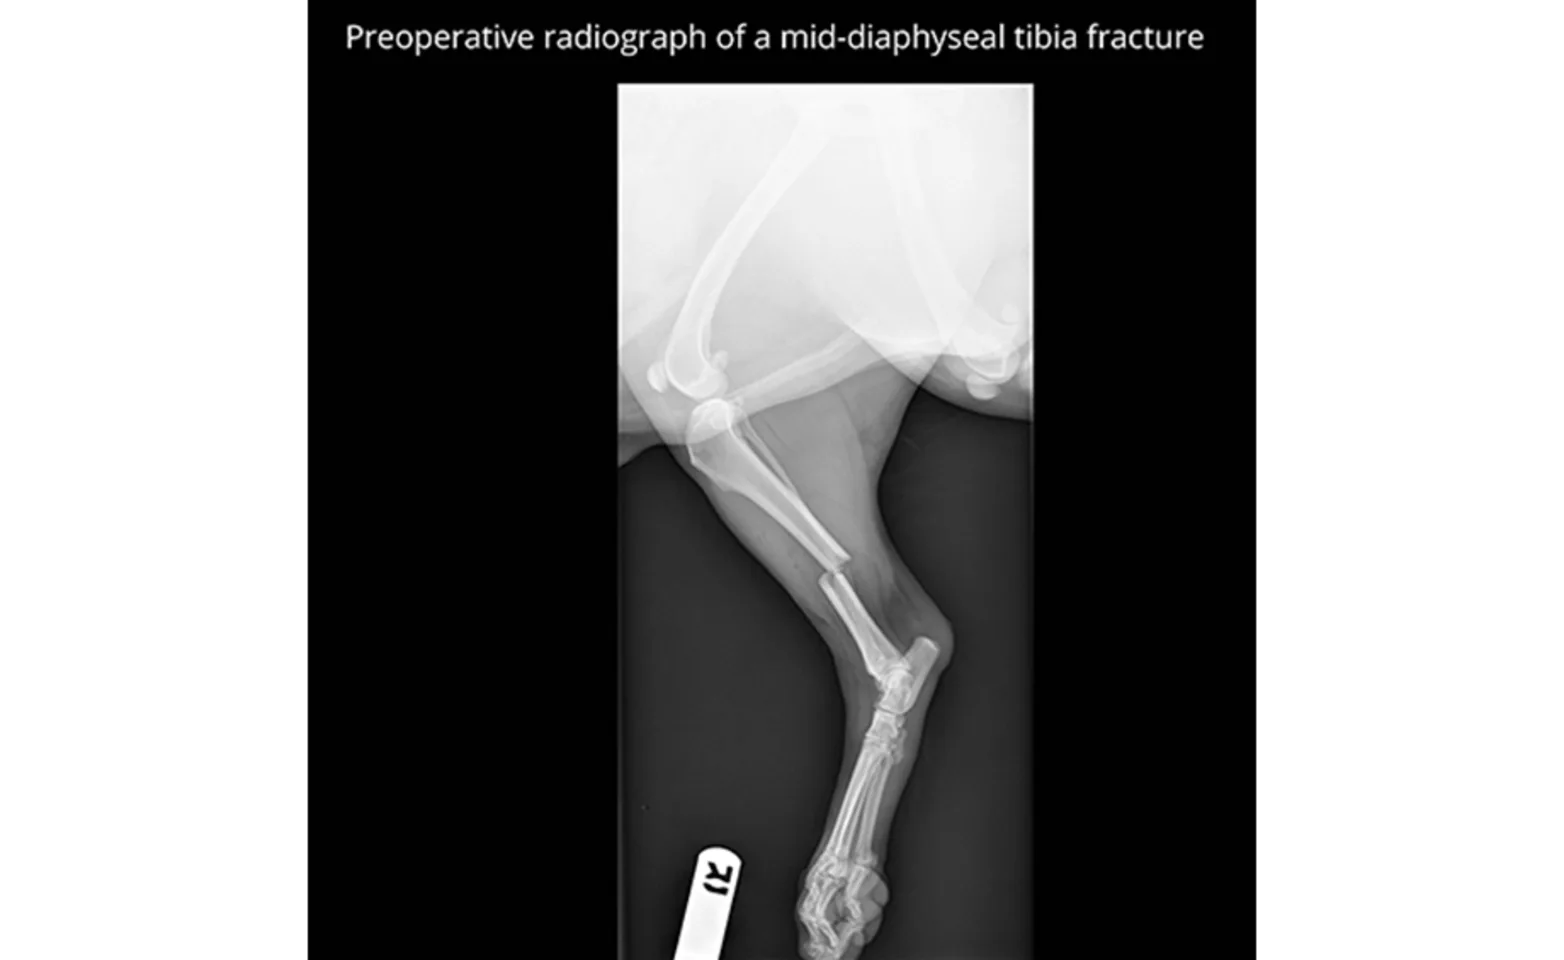

A fracture can seem like a devastating injury for your pet. Fortunately, the majority of fractures are fixable and carry a good long-term prognosis. The method of fracture repair will depend on the bone or bones that are involved. The most common methods of fracture stabilization are performed with bone plates, screws, and pins. The average time for a fracture to heal is about 8-10 weeks but may be shorter for young patients, or slightly longer for geriatric patients. More recently, certain fractures are being repaired in a minimally invasive fashion. This method uses intra-operative imaging, called fluoroscopy, to evaluate the bone while it is being aligned and stabilized with implants. With the use of fluoroscopy, incisions can be much smaller and the blood supply to the bone is better preserved. This type of fracture repair is usually referred to as “Minimally Invasive Plate Osteosynthesis” or “MIPO”.

A fracture and patient must meet very specific criteria to be a candidate for non-surgical management with a cast or splint. A very common fracture seen in veterinary patients is a break in the lower forelimb bones (radius and ulna), and usually this occurs in small breed dogs. This is a fracture that should always be managed surgically, as studies have shown a very high rate of complications when they are managed non-surgically.